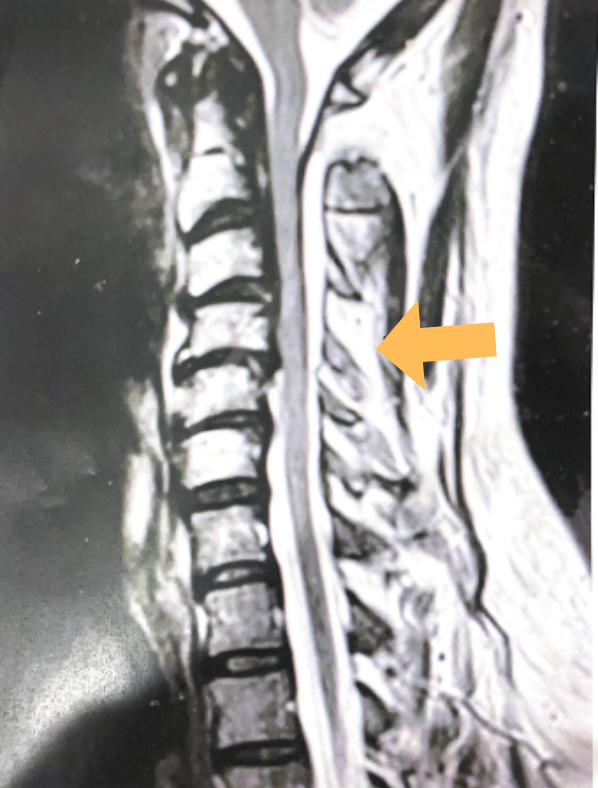

(1b) Hyperintense signal (arrow) at the C3-4 interspinous space consistent with ruptured interspinous ligament,C4-5 (Fig. 1a and 1b).

The fluid was possibly consistent with CSF versus chronic hematoma. The patient was also noted to have a high signal within the interspinous space of C3-C4. This high signal was consistent with a ruptured C3-4 interspinous ligament. Cervical flexion-extension x-rays demonstrated 6 mm of widening of the C3-4 interspinous space on flexion x-ray consistent with cervical instability (Fig. 2a and 2b).